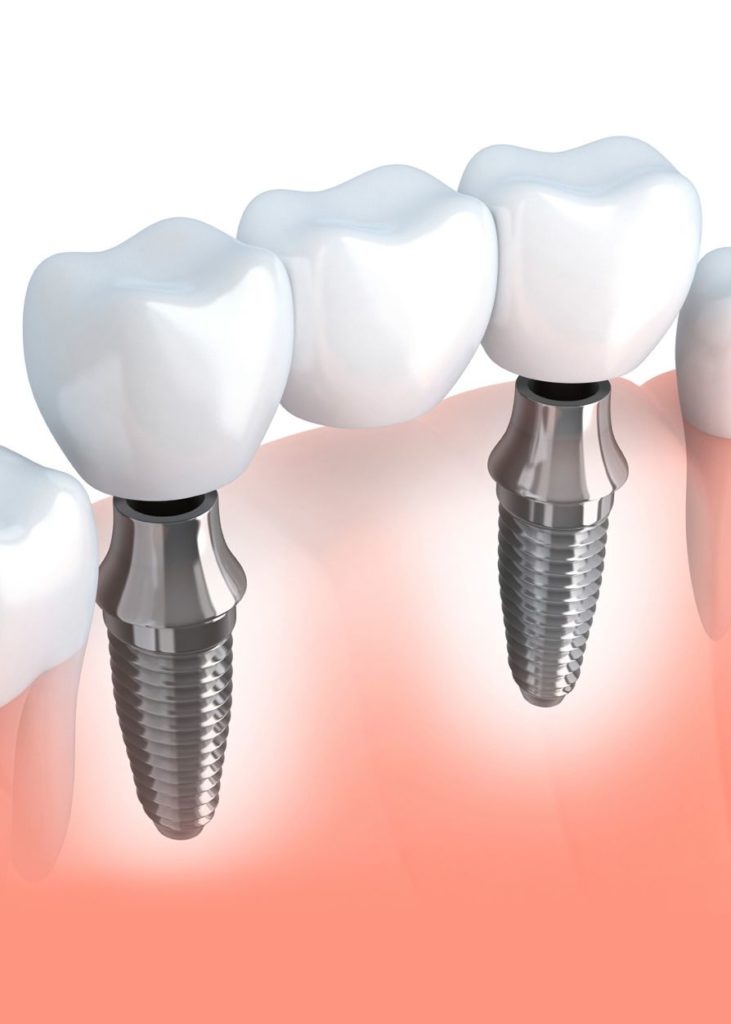

pngtree.comDental Implant Bridges | Implant-Supported Bridges

pngtree.comDental Implant Bridges | Implant-Supported Bridges

familydentistottawa.comimplant bridges prothetik corone ponti protetyka langheinrich implantologie zahnarzt zahnersatz protetyczne leczenie dr anchored uhlmann zahnarztpraxis

familydentistottawa.comimplant bridges prothetik corone ponti protetyka langheinrich implantologie zahnarzt zahnersatz protetyczne leczenie dr anchored uhlmann zahnarztpraxis

Dental Bridges - Implantcenter Dentistry UK

implantcenter-dentistry.co.ukimplant dental bridges bridge implants restorations supported dentistry crown tooth vs

implantcenter-dentistry.co.ukimplant dental bridges bridge implants restorations supported dentistry crown tooth vs